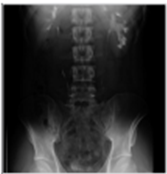

Common iliac artery의 dissecting aneurysm 환자로 전방의 요관을 압박하여 수신증이 발생함.

- 부인과 수술 후 발견된 수신증으로 경피적신루가 설치된 환자임. AGP에서 midureter에 폐색부위가 관찰된다. RGP를 동시에 시행하여 요관협착의 정도를 정확히 알수 있다.

상부신배누두부협착환자의 사진으로 좌측그림은 상부신배만 조영이 되는 소견임. 하부신배에 신루설치를하여 조영제를 투입하면 상부신배누두부 협착부위 및 신우의 모양, 요관의 위치를 정확히 알수 있어 우측과 같이 풍선확장술을 안전하게 시행 할 수 있다.